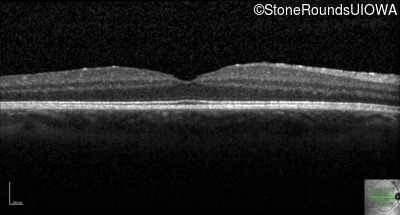

Optical Coherence Tomography - Right - 20/20

Exemplar / OCT Stack

Optical Coherence Tomography - Left - 20/20 -2